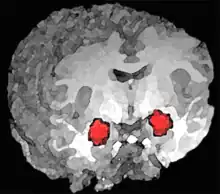

- Amígdala cerebral. Algunos estudios basados en diversas técnicas de exploración por imágenes muestran que los mecanismos cerebrales subyacentes a la impulsividad, inestabilidad emocional, agresividad, ira y emociones negativas podrían estar en una desregulación de los circuitos neuronales que modulan las emociones. En especial, se han observado pequeñas diferencias individuales en como se regula la amígdala, un núcleo cerebral que desencadena el pánico o la ira en respuesta a estímulos de peligro procedentes de otras áreas cerebrales. Algunos individuos tienen dificultades para inhibir esta respuesta desde el área prefrontal. Se sabe que el abuso de substancias o el estrés empeoran esta capacidad de inhibición.[21][22] En 2003 se realizó un estudio sobre afectados de TLP, viendo que mostraban una actividad significativamente superior en la amígdala izquierda, en comparación con sujetos normales. Algunos pacientes con este trastorno incluso tenían dificultades para clasificar caras neutras, que veían como amenazantes.[23]

Otros estudios han encontrado una disminución de tamaño significativa en el volumen del hipocampo y de la amígdala en síndromes con síntomas disociativos.[25] La diferencia de tamaño del hipocampo, una estructura cerebral relacionada con la memoria, se ha establecido en un promedio de un 16 % menor (Driesden y otros, 2000) lo cual podría explicar dos rasgos asociados al TLP, la dificultad para aprender de la experiencia y los problemas para generar una identidad. En cuanto a la disminución de volumen en la amígdala, estudios posteriores llevados a cabo por Tebartz (2007) confirmaron las cifras iniciales, encontrando un aumento correspondiente en la amígdala izquierda del 17 % en los contenidos de creatina, posiblemente para compensar un deterioro en las redes neuronales.[26]